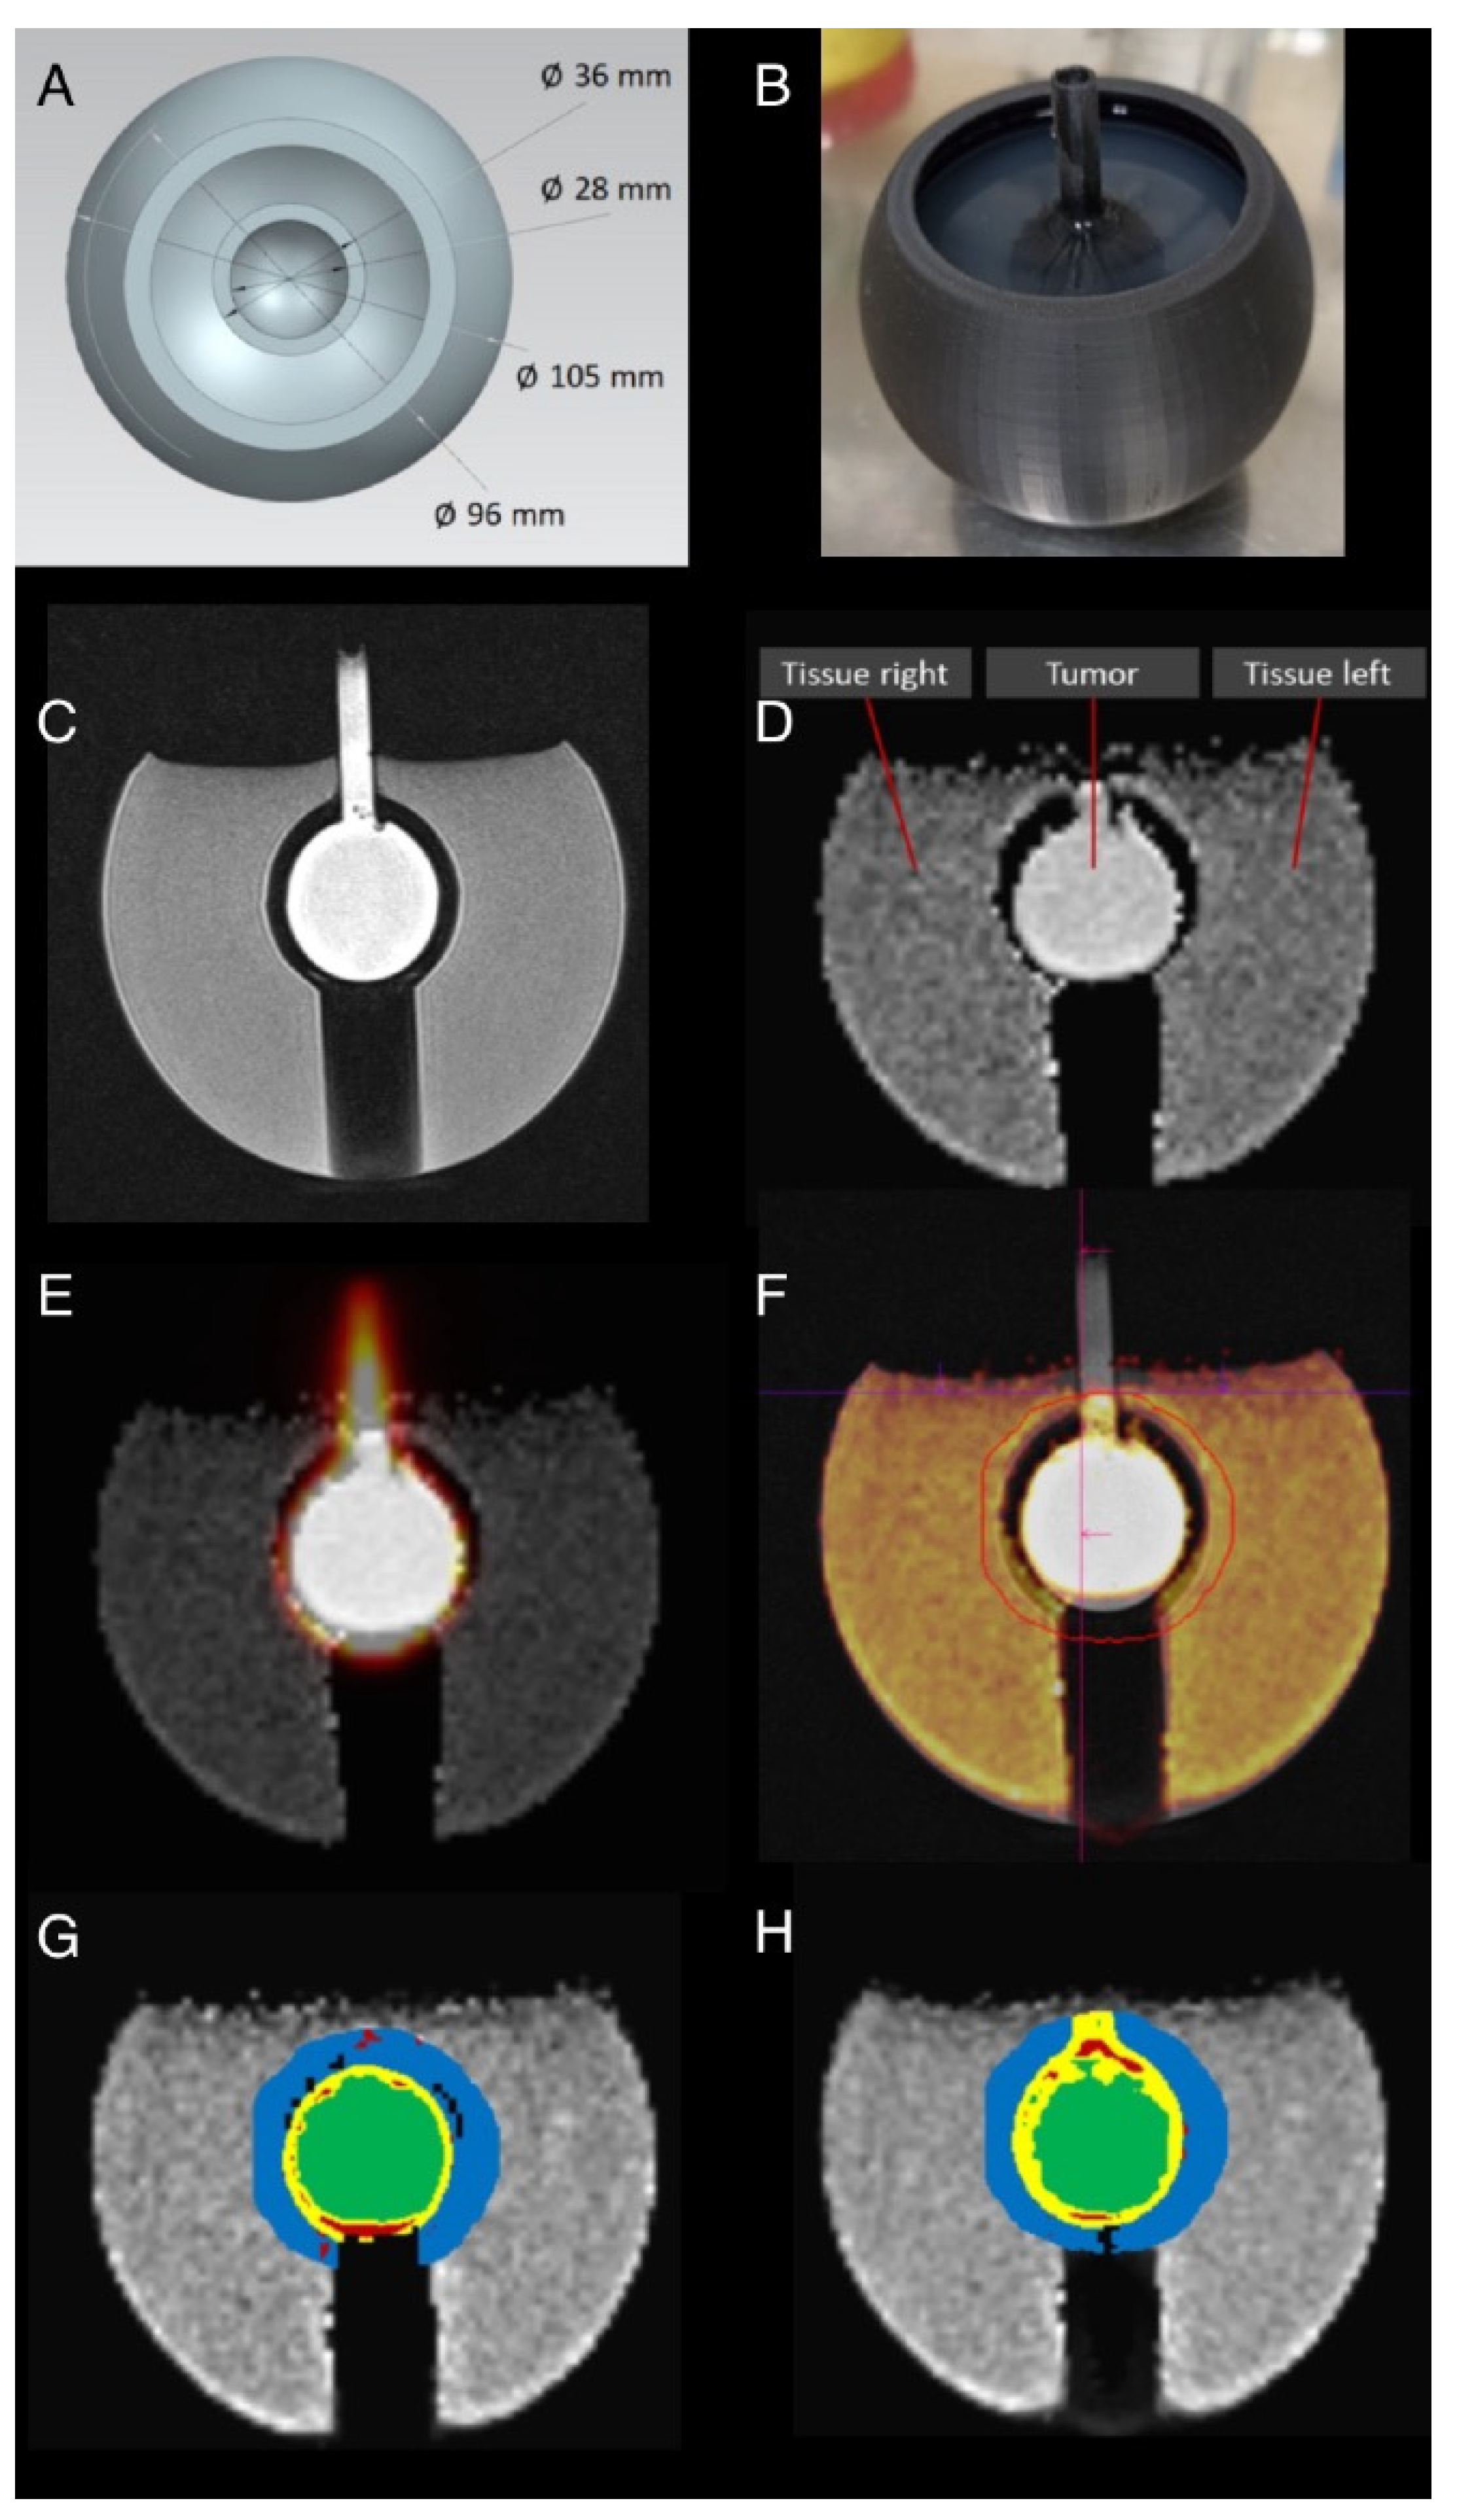

2.1. Phantom Generation

2.2. Sector Phantom

2.3. Tumor Phantom

2.4. Phantom MR and PET Measurements

3.3. Sphere and Tumor Phantoms